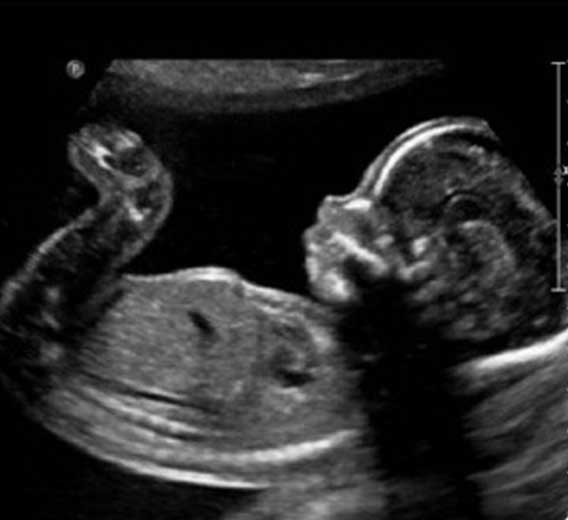

A ultrassonografia (ou ecografia) é um método diagnóstico que aproveita o eco produzido pelo som para ver em tempo real as reflexões produzidas pelas estruturas e órgãos do organismo.

Os aparelhos de ultrassom em geral utilizam uma frequência variada dependendo do tipo de transdutor, desde 2 até 14 MHz, emitindo através de uma fonte de cristal piezoelétrico que fica em contato com a pele e recebendo os ecos gerados, que são interpretados através da computação gráfica.

Quanto maior a frequência maior a resolução obtida. Conforme a densidade e composição das estruturas a atenuação e mudança de fase dos sinais emitidos varia, sendo possível a tradução em uma escala de cinza, que formará a imagem dos órgãos internos.

A ultrassonografia permite também, através do efeito doppler, se conhecer o sentido e a velocidade de fluxos sanguíneos. Por não utilizar radiação ionizante, como na radiografia e na tomografia computadorizada, é um método inócuo, barato e ideal para avaliar gestantes e mulheres em idade procriativa.